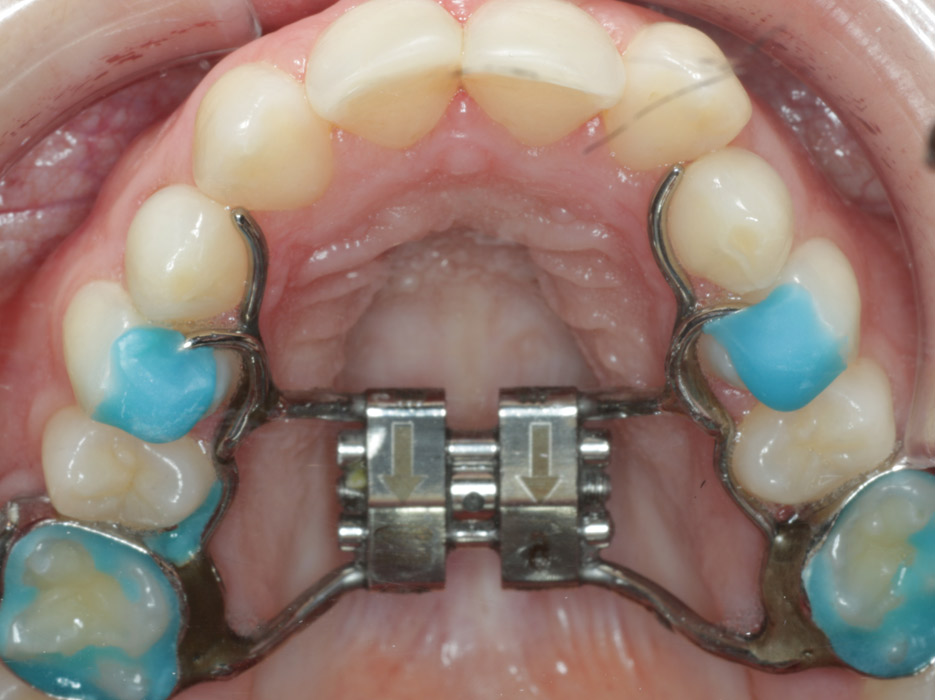

La ortodoncia es el método más empleado para abordar esta problemática. Lo ideal sería utilizarla en edades tempranas, esto dependerá de la fase de crecimiento del paciente. En ese momento vital hay más posibilidades de guiar correctamente el crecimiento de los dientes. También es más fácil moldear los huesos dentales, su tamaño y posición. El ortodoncista, haciendo uso de la ortodoncia interceptiva, puede mover la estructura ósea para que esta tenga un desarrollo adecuado.

Aunque se han visto de forma separada, lo más recomendable es aunar ambas soluciones. Por norma general en pacientes adultos, la operación ortognática va acompañada de un tratamiento posterior de ortodoncia. Suele mantenerse durante dos años, aunque esto dependerá de las características concretas del paciente.